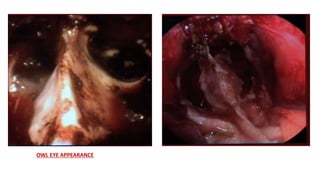

This document discusses the microanatomy of the sellar and suprasellar regions as well as operative approaches for accessing these areas. It describes the bones, venous connections, arterial relationships and incisura spaces in the regions. Several surgical approaches are mentioned, including sublabial, transseptal, endonasal, and subfrontal transfrontal transsphenoidal approaches. Key anatomical structures like the optic chiasm, carotid protuberance, cavernous sinus and clival indentation are located using an "owl eye" panoramic view of the fetal face mimicking centers.